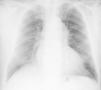

A 63-year-old man presented to the hospital with gradual-onset hoarseness of three months’ duration. He had a history of smoking assessed at 58 pack-years, and no other symptoms such as cough, dyspnea or weight loss. His heart rate was 60 beats/min and blood pressure was 159/67 mmHg; the cardiac exam revealed a diastolic murmur in the aortic area. Indirect laryngoscopy revealed a paralyzed left vocal cord in paramedian position. The chest X-ray (Figure 1) showed a slight mediastinal bulge adjacent to the aortic knuckle but no pulmonary mass.